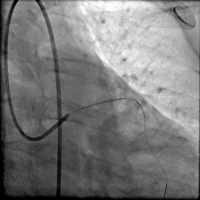

第二次手术过程

手术时间: 2016年11月。

术中用药: 术中肝素6000单位。

造影结果: 左前降支近段闭塞,回旋支中远段90%狭窄。

手术过程(一): 将Fielder XT 导丝送入回旋支远端真腔,沿回旋支导丝送入Trek 2.5×20 mm球囊到回旋支中段8 atm×10 s预扩,沿导丝Firebird 2.5×29 mm药物支架一枚到回旋支中远段8 atm×12 s释放。

手术过程(三): 微导管支持下ASAHI Gaia 1st 导丝通过前降支真腔。

手术过程(五): 沿导丝送入Firebird 2.5×33 mm药物支架一枚至前降支中段10 atm×12 s释放,沿导丝送入Firebird 3.0×23 mm药物支架一枚至前降支近段14 atm×12s释放。